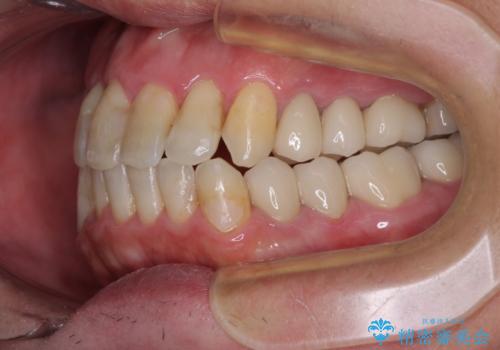

- 飛び出している上顎前歯と、奥歯に多くある銀歯を気にして来院された患者様です。

マウスピースで矯正を行いたい反面、一旦早めに前歯を整えたいというご希望があったため、まずは上顎前歯をワイヤー装置で整え、その後インビザラインにて仕上げていくこととしました。

矯正治療後には、奥歯の銀歯をすべてセラミックにて補綴治療することとしました。

ワイヤー矯正を併用したことで、上顎前歯はあっという間に整いました。

補綴治療にあたり、痛みのある歯に対して根管治療を行うこととしましたが、処置が必要な歯が多かったため、期間を要しました。

補綴治療中に前歯のデコボコが戻ってしまったため、補綴治療後にインビザラインを1セット追加して仕上げました。